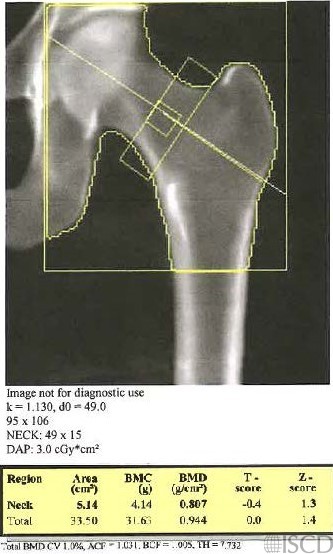

This image shows a Hologic left hip DXA scan. .

Increasing the length of the femur scan field does not affect proximal hip bone mineral density on both GE/Lunar and Hologic scanners (references below). There is an extended Hologic hip scan that is ordered to look for atypical femoral fractures.